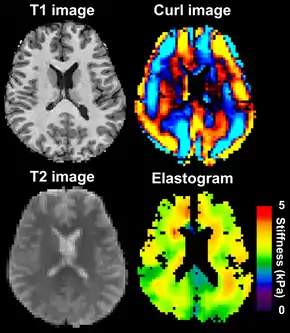

MRE is conducted in three steps: first, a mechanical vibrator is used on the surface of the patient's body to generate shear waves that travel into the patient's deeper tissues; second, an MRI acquisition sequence measures the propagation and velocity of the waves; and finally this information is processed by an inversion algorithm to quantitatively infer and map tissue stiffness in 3-D.[2][3] This stiffness map is called an elastogram, and is the final output of MRE, along with conventional 3-D MRI images as shown on the right.[2]

|  Magnetic resonance elastography of the brain. A T1 weighted anatomical image is shown in the top-left, and the corresponding T2 weighted image from the MRE data is shown in the bottom-left. The wave image used to make the elastogram is shown in the top-right, and the resulting elastogram is in the bottom-right. | |

MRE of the brain [27] was first presented in the early 2000s.[28][29] Elastogram measures have been correlated with memory tasks,[30] fitness measures,[31] and progression of various neurodegenerative conditions.[27] For example, regional and global decreases in brain viscoelasticity have been observed in Alzheimer’s disease[32][33] and multiple sclerosis.[34][35] It has been found that as the brain ages, it loses its viscoelastic integrity due to degeneration of neurons and oligodendrocytes.[36][37] A recent study looked into both the isotropic and anisotropic stiffness in brain and found a correlation between the two and with age, particularly in gray matter.[38]